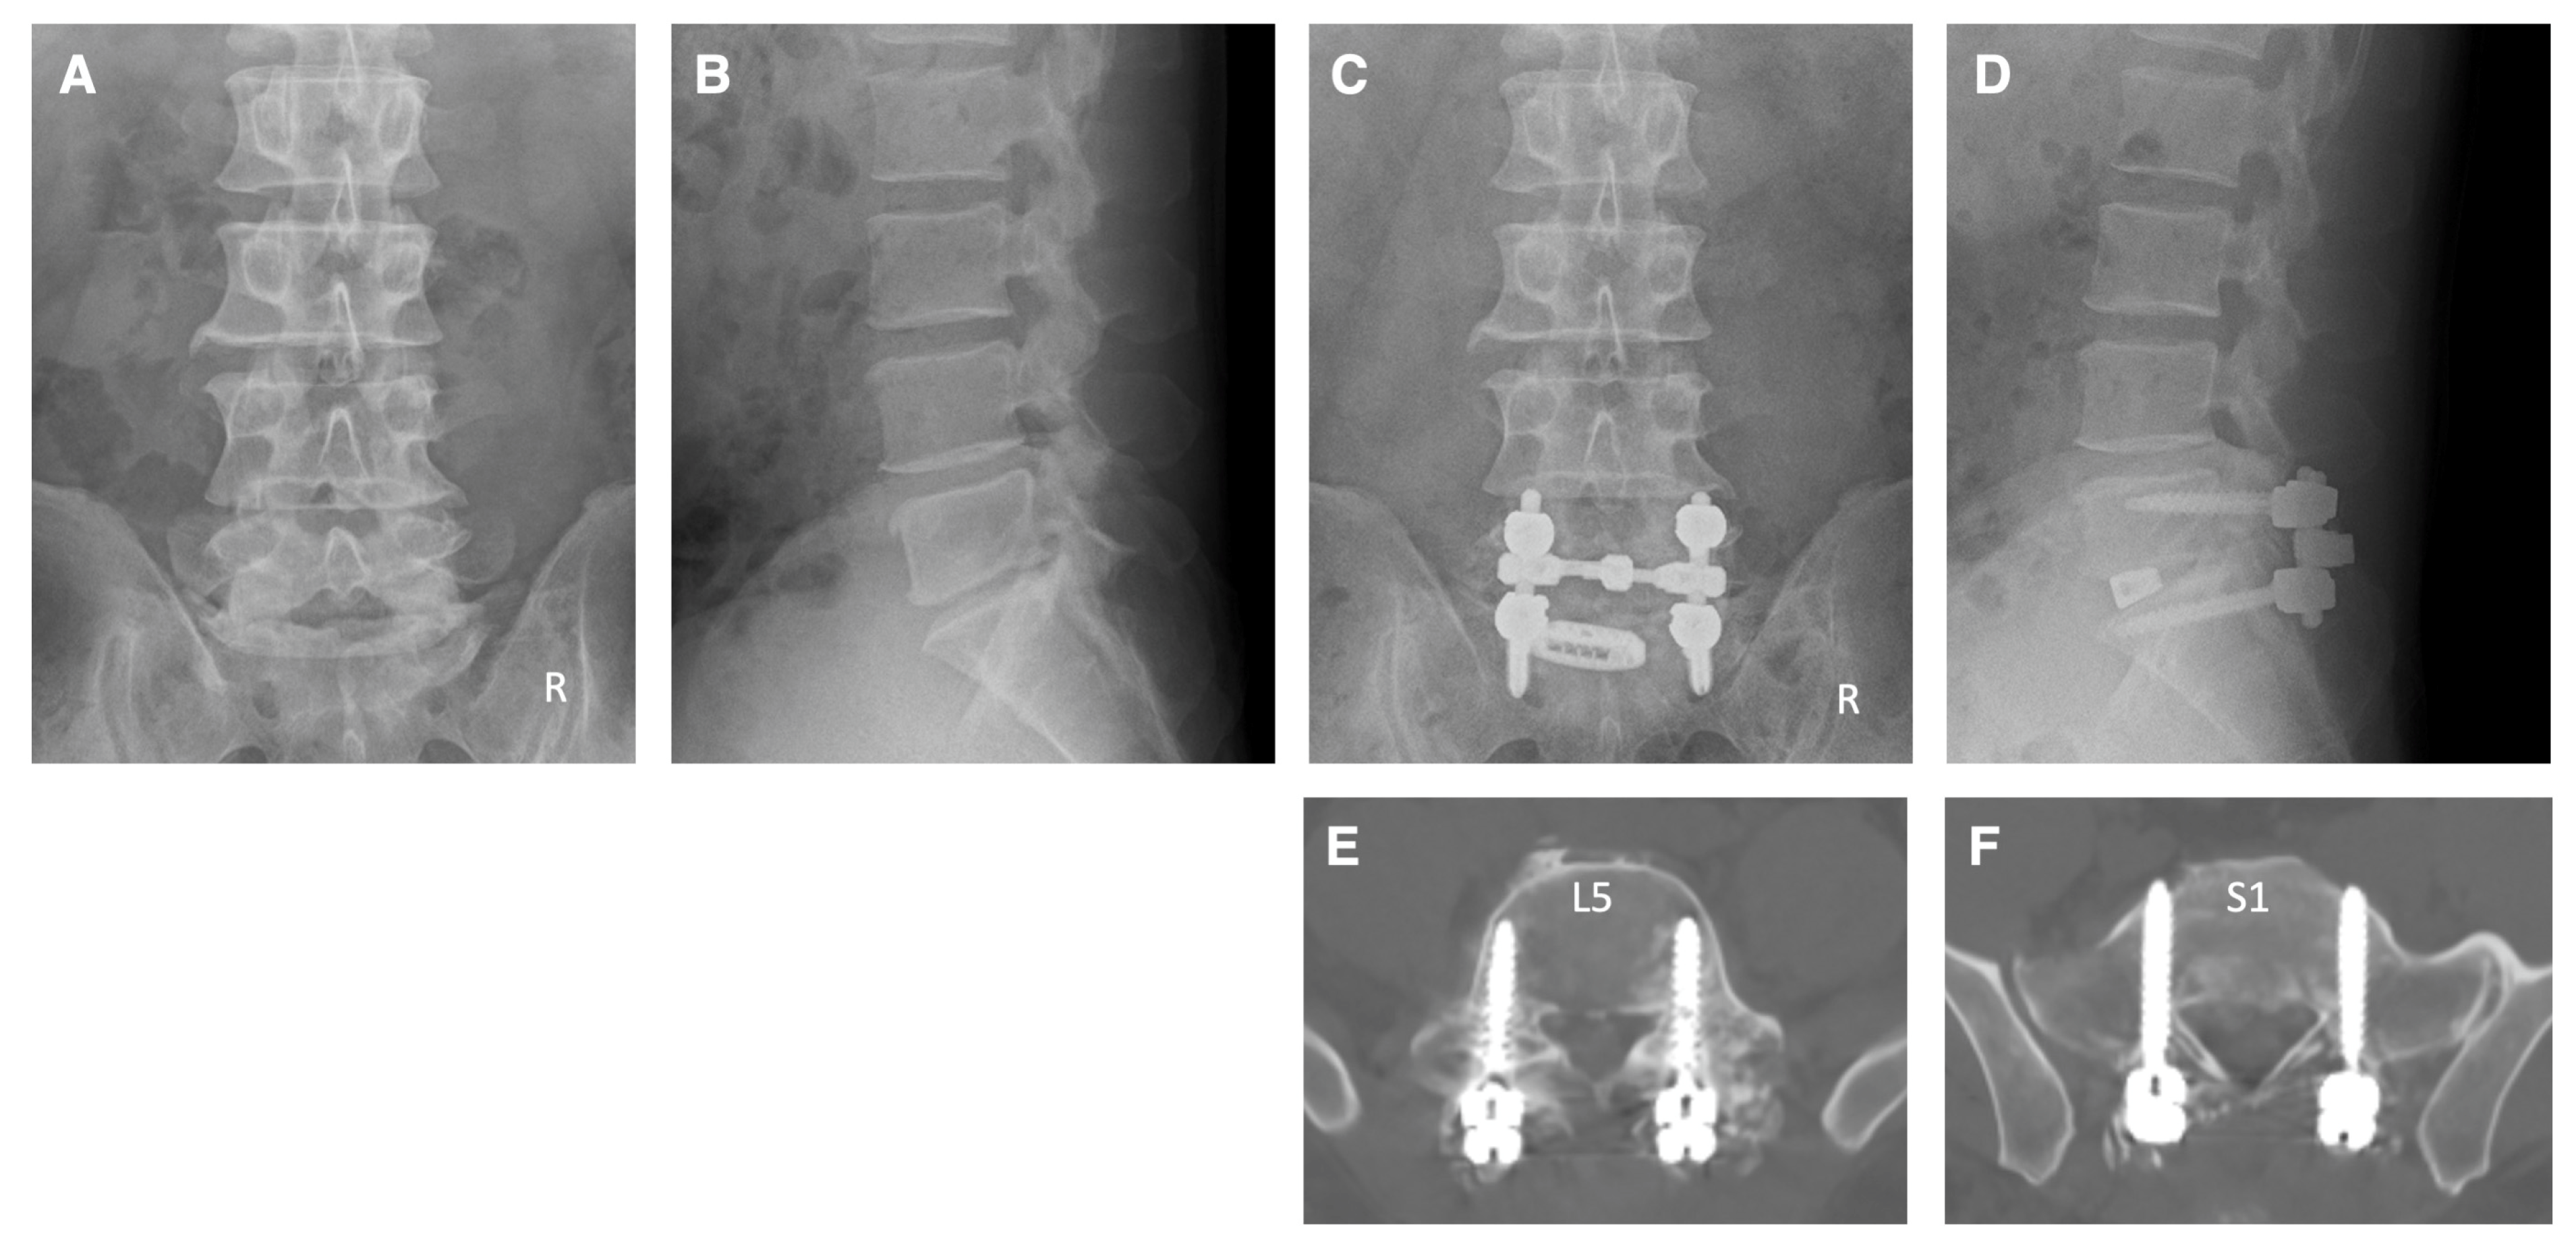

4. Illustrative Cases